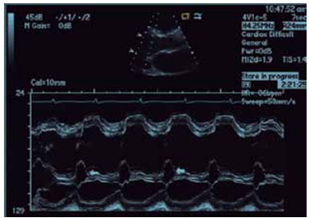

Observe a imagem.

(Arquivo pessoal; imagem utilizada com autorização)

A imagem sugere a presença de